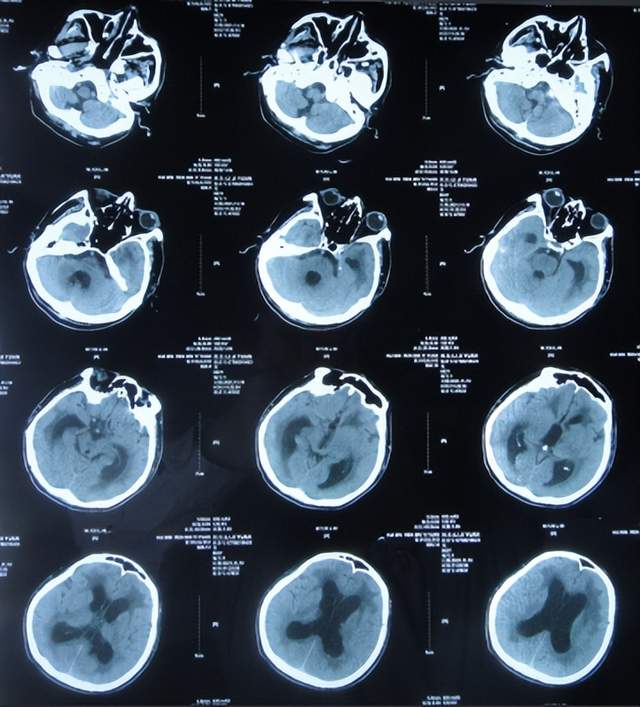

患者于2021年9月2日突发昏迷,急送至当地的山东省滨州市惠民县某医院,查头颅CT示脑出血破入脑室(图-1),急诊行双侧脑室外引流术;脑出血后血压偏低,给予输注入人血白蛋白。

图-1:2021年9月2日头颅CT

术后次日即2021年9月3日,患者意识转清醒,能简单言语,肢体可以遵嘱抬起;查头颅CT示双侧脑室引流术后,脑室积血(图-2)。

图-2:2021年9月3日头颅CT

双侧脑室外引流术后3天即2021年9月5日,查头颅CT示脑室内积血减少(图-3)。

图-3:2021年9月5日头颅CT

双侧脑室外引流术后6天即2021年9月8日,再次查头颅CT示仍有少量积血(图-4);给予常规拔除了双侧脑室外引流管,同时进行了腰大池引流术。

图-4:2021年9月8日头颅CT